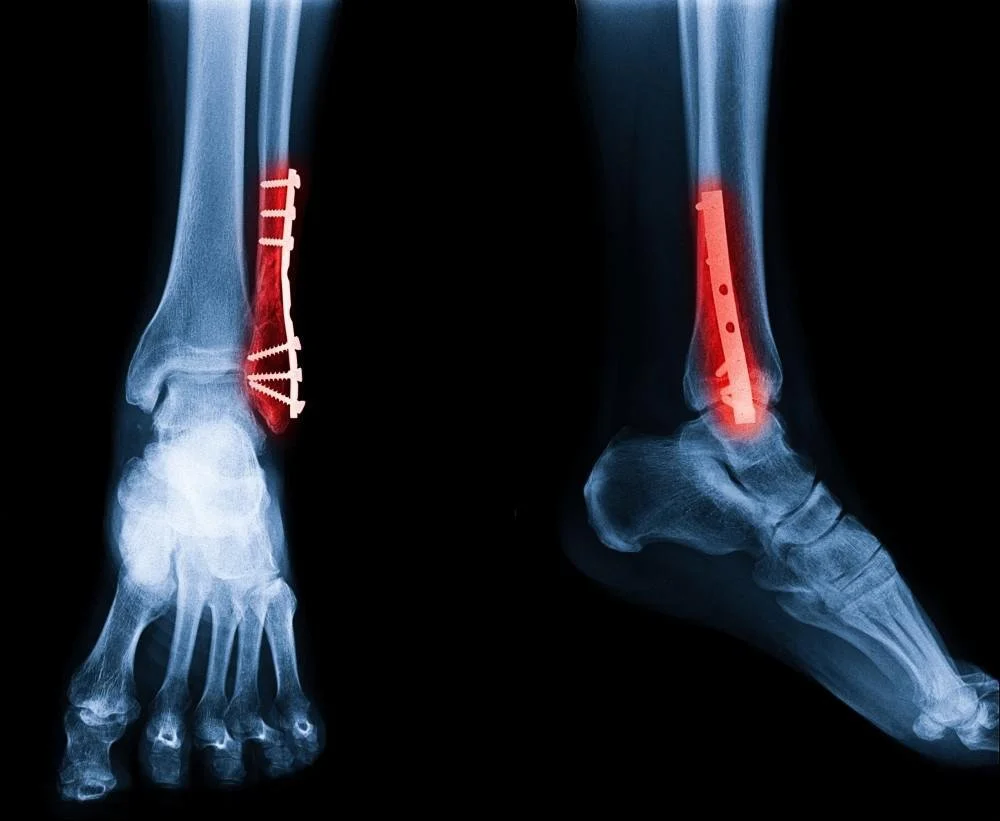

We strive to restore your foot & ankle function using the the least invasive treatment possible so you can get back to on your feet. Dr. Henry uses both nonoperative treatments and surgeries to get you back to doing what you love. These are just some of the procedures Dr. Henry specializes in.

Through a joint decision-making process, we may recommend surgical treatment if we believe the potential benefits outweigh the risks. For patients with chronic (long-term) conditions, the decision for surgery may come after a period of nonoperative treatment, including shoewear changes, orthotics (shoe inserts), ankle/foot braces, physical therapy, medication, activity optimization, and injections. You will discuss this in your consultation with Dr. Henry.